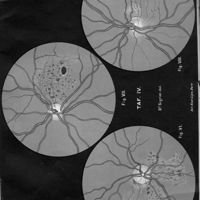

Ophthalmoskopische Studien

- Ophthalmoskopische Studien

- Mitteilungen aus kliniken und medicinischen Instituten der Schweiz, Vol. 3, pp. 545-82

- Siegrist - Hutchinson (syndrome de)